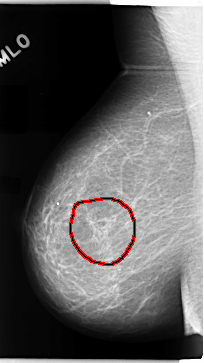

C_0073_1.RIGHT_MLO

FILE: C_0073_1.RIGHT_MLO.OVERLAY

TOTAL_ABNORMALITIES 1

ABNORMALITY 1

LESION_TYPE MASS SHAPE ARCHITECTURAL_DISTORTION MARGINS N/A

ASSESSMENT 3

SUBTLETY 1

PATHOLOGY MALIGNANT

TOTAL_OUTLINES 1

BOUNDARY